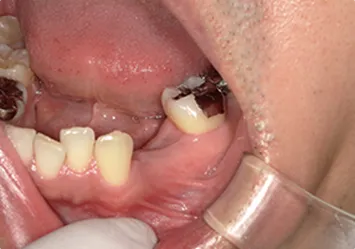

治療前

治療前写真 恵比寿南DENTAL 治療前写真 恵比寿南DENTAL

施術内容

【20代女性】

右下7番の歯根破折してしまい保存不可能となってしまった歯を抜歯し、インプラント埋入

治療期間

5ヶ月

リスク

術中の不可抗力によるトラブル(出血など)、術後注意事項を守らないことによる疼痛、感染、上部構造装着後口腔内清掃を怠ったことによるインプラント周囲組織の炎症

副作用

治療後の口腔内清掃、及びメインテナンスを怠ったことによるインプラント周囲粘膜炎またはインプラント周囲炎

費用

インプラント埋入:30万円

ジルコニアクラウン:12万円